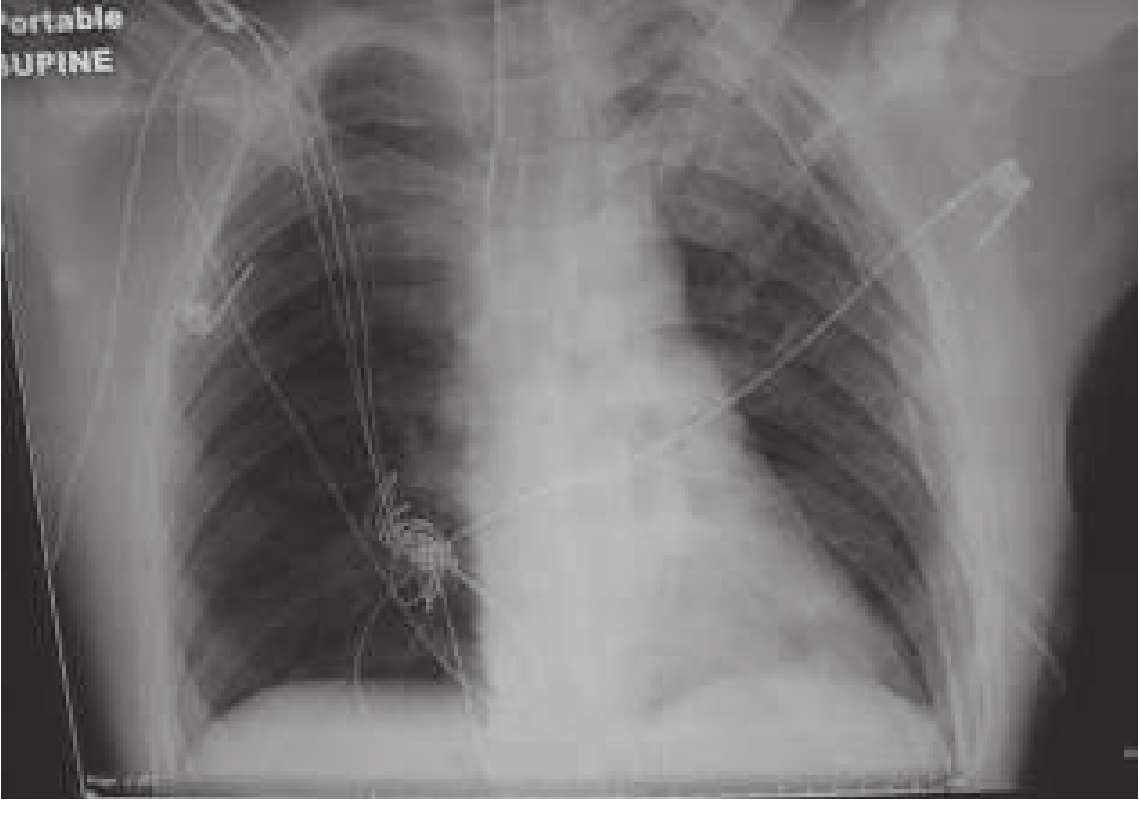

Tension pneumothorax CXR

Tension pneumothorax with resolution after left-sided tube thoracostomy — Rosen's Emergency Medicine